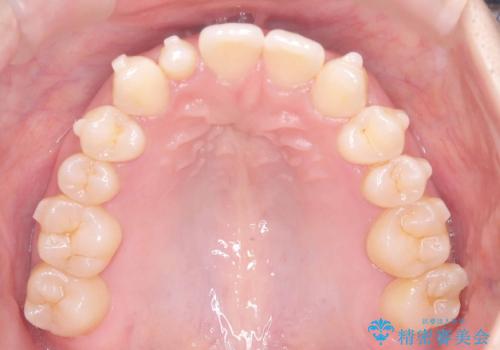

- 歯のデコボコと右上2番の歯の形が気になることを主訴に来院された患者様です。

軽度の叢生(凸凹)であったため、インビザラインのライトパッケージを用いて歯並びを改善しました。その後、右上2番はオールセラミッククラウンにより形態を回復し、審美性を向上させました。